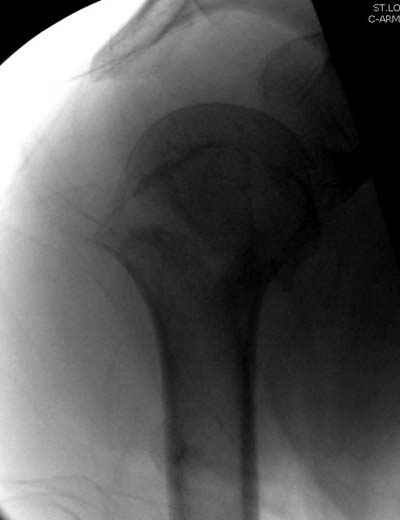

Уважаемые коллеги,

Спасибо за участие в дискуссии -перелом шейки плеча, для себя я прояснил многие технические моменты...

Посылаю послеоперационные Рг граммы.

Всего Доброго,

Евгений И Чекашкин

Поздравляю, получилось просто замечательно. Если можно, расскажи чуть подробнее, как делали - как вправляли, как вводили спицы, поворачивали ли их?

Спасибо за поздравления:-))

Я и сам доволен результатом. В предпоследнем письме я кратко описал ход операции - закрыто репонировать не удалось( 2 недели с момента травмы и 1 неделя после неудачной репозиции) после удаления пучков спиц, пришлось сделать - 2см разрез на уровне перелома и с помощью периостального элеватора (золотое правило механики) *одеть* головку на дистальный отломок.

Спицы проводил через старые отверстия, вращая пучок импактором- направителем при его введении в головку.